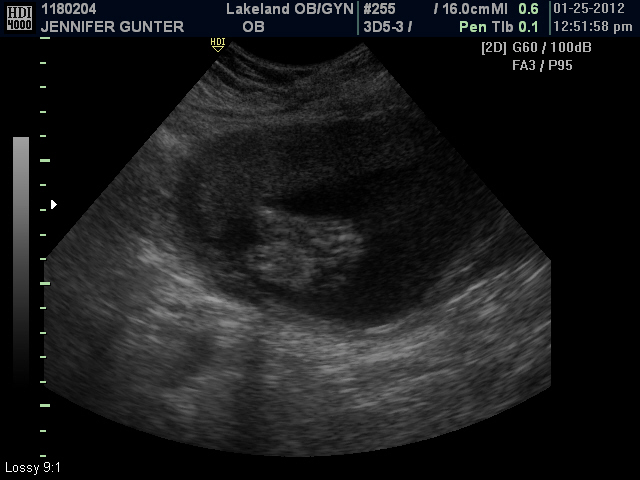

Wednesday, January 25, 2012

Today we had another growth ultrasound. You are approximently 1 pound 10oz now. everything is growing within normal limits according to the tech. Your brothers and your dad came with me. This was the 1st time you dad got to see you on the ultrasound screen.